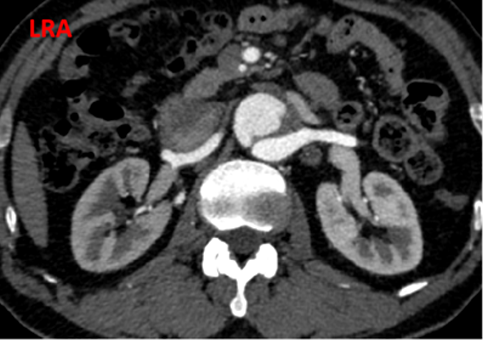

夹层近端封闭良好。夹层动脉瘤累及整个内脏区动脉,腹腔干、肠系膜上动脉假腔供血,腹腔干开口重度狭窄;右肾动脉真假腔供血,以假腔为主;左肾动脉真腔供血。肾下腹主动脉段无裂口,右侧髂外动脉存在裂口。

CT影像